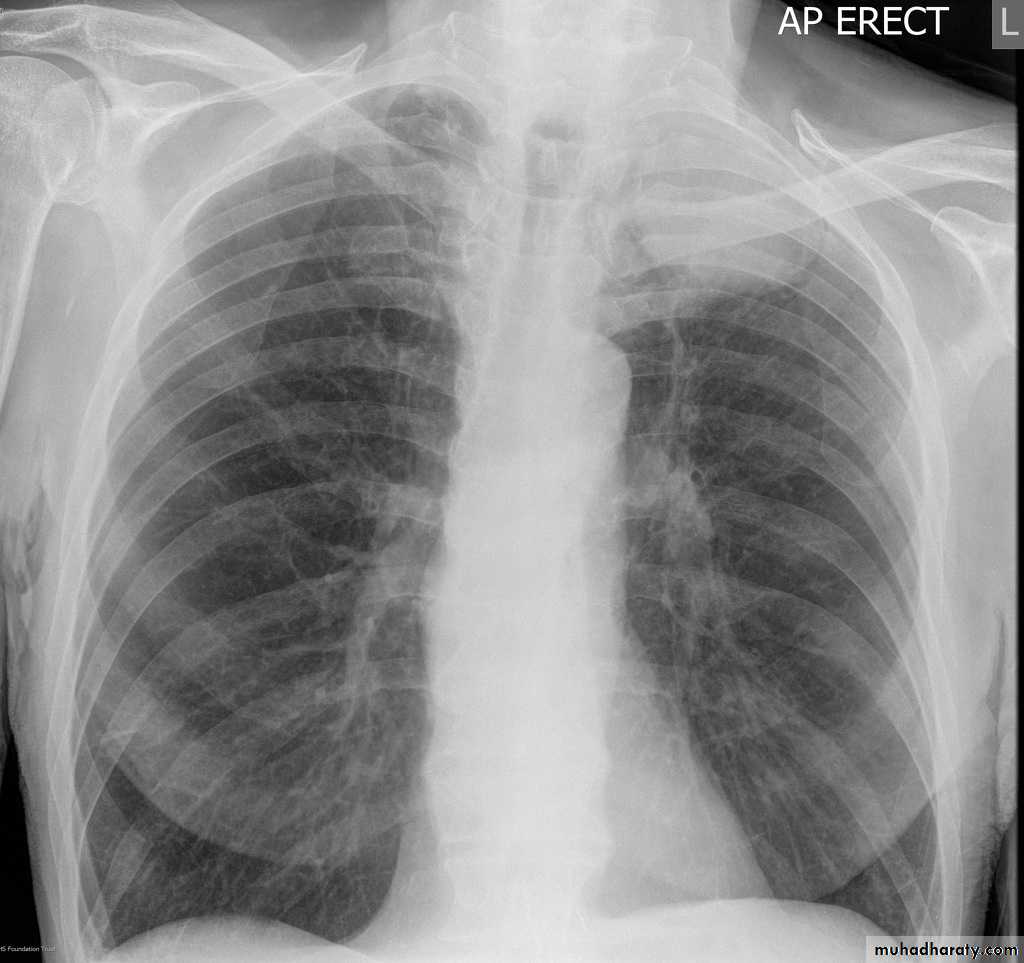

Left lower lobe collapse has distinctive features, and can be readily identified on frontal chest radiographs, provided attention is paid to the normal cardiomediastinal contours. The shadow cast by the heart does however make it harder to see than the right lower lobe collapse

Radiographic features

Left lower lobe collapseis readily identified in a well penetrated film of a patient with normal sized heart, but can be challenging in the typical patient with collapse, namely unwell patients, with portable (AP) often under-penetrated films, often with concomitant cardiomegaly. Features to be observed include :

triangular opacity in the posteromedial aspect of the left lung

edge of collapsed lung may create a 'double cardiac contour'

left hilum will be depressed

loss of the normal left hemidaphgragmatic outline

loss of the outline of the descending aorta